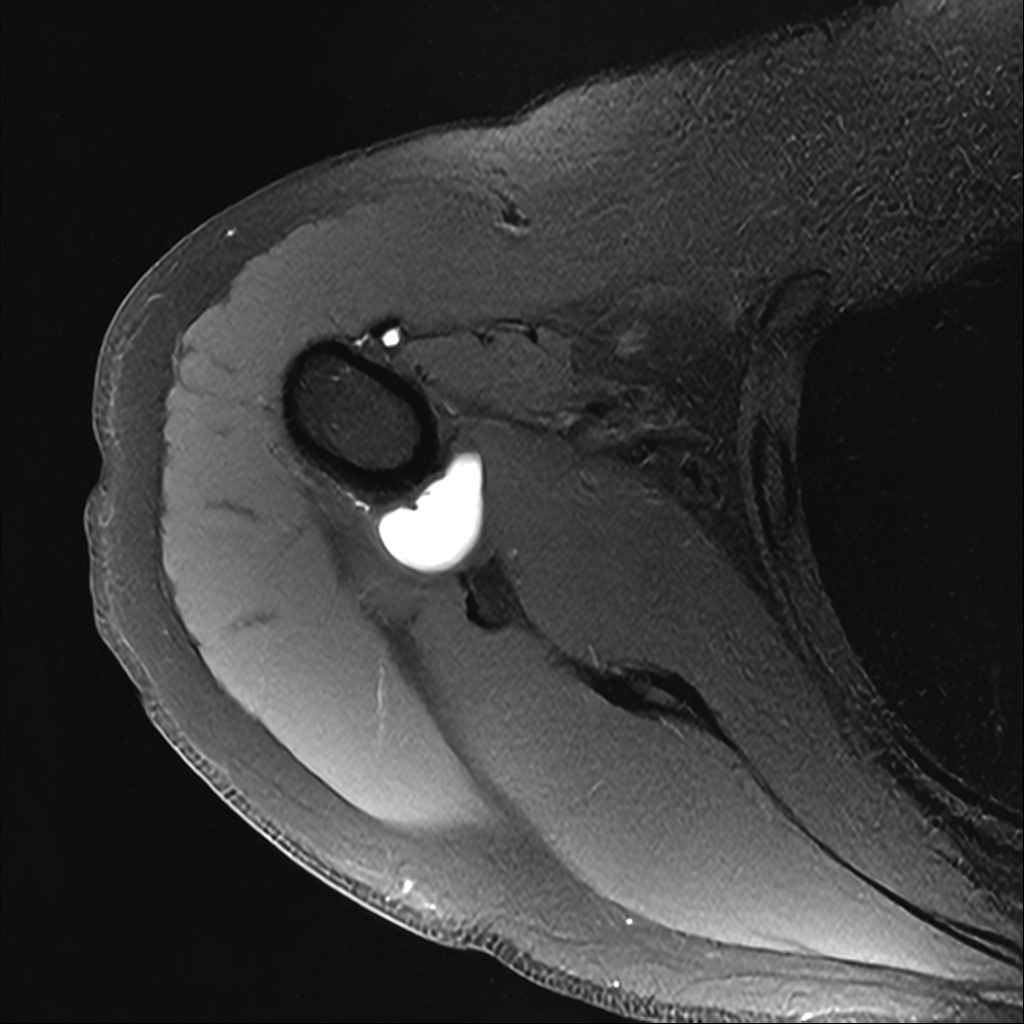

Mri 단면 영상으로 보아 어깨 관절 부위에서 이상 신호가 관찰되고 이는 관절 와순 파열의 가능성을 시사할 수 있습니다.

하지만 이영상만으로 정확한 진단은 불가능하고 정밀한 판단을 위해선 전체 시퀀스와 영상의학과 전문의의 공식판독이 필요합니다 특히 와순 파열은 위치와 동반 병변에 따라 해석이 달라집니다!